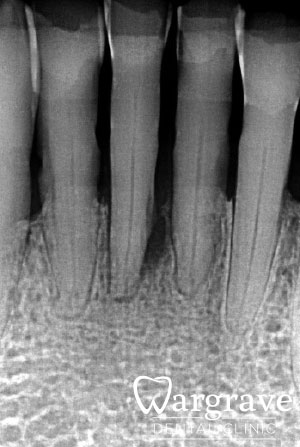

Before

In this case the patient’s lower incisors had lost 60-70% of their supporting bone. The four failed incisors were extracted and replaced with a 4 unit implant bridge supported by two implants